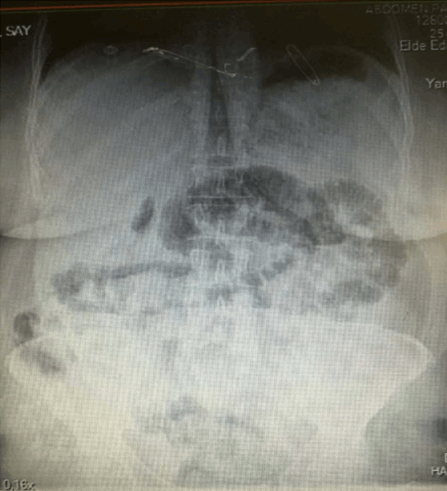

A 60-year-old female patient was admitted to the emergency service and presented with abdominal pain. Symptoms such as total constipation, nausea and vomiting were present for three days. She had had similar history of these symptoms previously and she had been hospitalized because of those symptoms. At that time, laboratory and imaging studies revealed no pathological finding one year ago. She had history of hypertension. Abdominal examination revealed abdominal distension and a palpable mass in her upper left quadrant. Laboratory studies were normal. Plain abdominal X-ray showed that there are air-fluid levels in small intestines (Figure 1). Abdominal CT revealed dilatation of small intestines and internal herniation (Figure 2). With these results explorative laparotomy was performed which showed a fixated membranous structure encapsulating all of the intraabdominal organs and not allowing to explore intraabdominal organs. The diagnosis was sclerosing encapsulated peritonitis according to explorative laparotomy. Adhesiotomy was partially applied. Physical examination was normal with spontaneous intestinal motility and normal defecation during the postoperative follow-up period. The patient was discharged from the hospital following uneventful course and appeared well in the outpatient visits.

Figure 1: X-ray showing air fluid levels in small intestine.